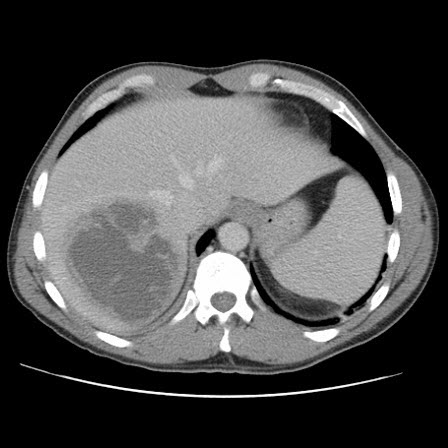

Aneurisma da aorta abdominal: tomografia computadorizada (TC) de um aneurisma da aorta abdominal roto

University of Michigan, mais especificamente os casos do Dr. Upchurch, representando os Departamentos de Cirurgia vascular e Radiologia